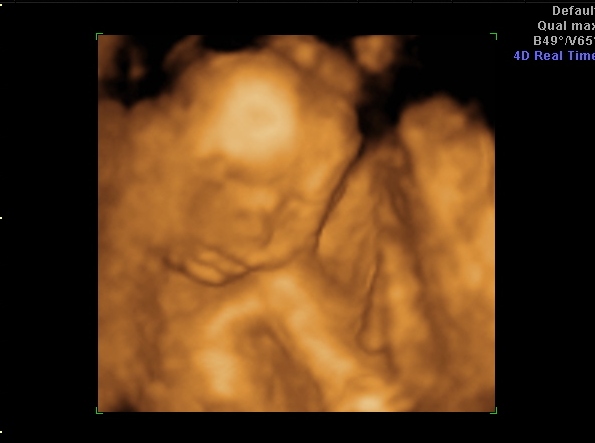

Köszönöm a jobbulás-hozzászólásokat, beváltak, a hasam tök oké végre, csak a babó rugdos óránként (megfordult, most bal oldalt van a feje és jobb oldalt érzem a csikizést